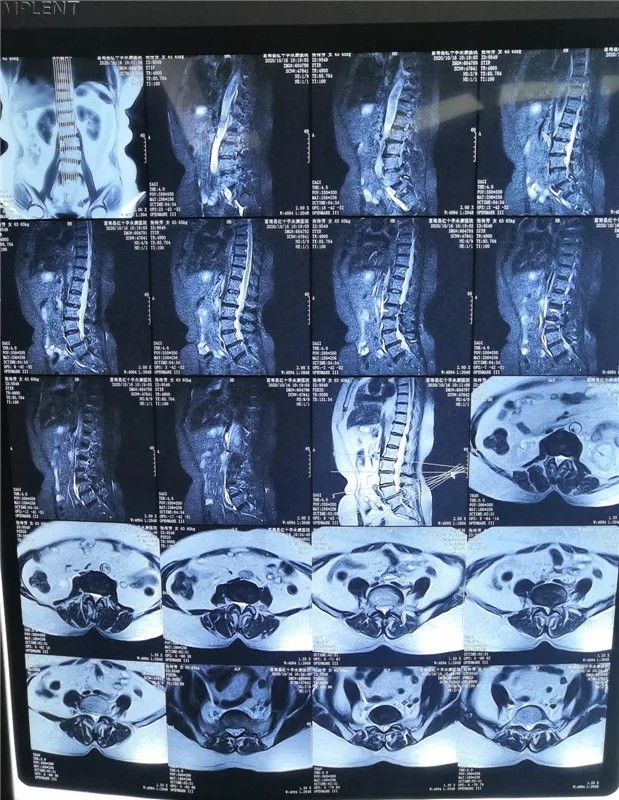

患 者:女,63岁。

主 诉:左下肢放射性疼痛1个月,入院治疗。

现病史:患者近1个月来无明显诱因下出现左下肢放射性疼痛,从臀部沿大腿后侧到小腿外侧,平卧加重,严重影响睡眠,在当地医院行各种保守治疗无效,为进一步治疗入院治疗。

查 体:双下肢皮肤无皮疹、水泡,双下肢肌力5级,直腿抬高试验阴性,末梢感觉正常,血运正常。VAS评分8分

影像资料:

诊 断:

腰椎管狭窄症;腰椎间盘突出症(L4/5);老年退变性侧弯。